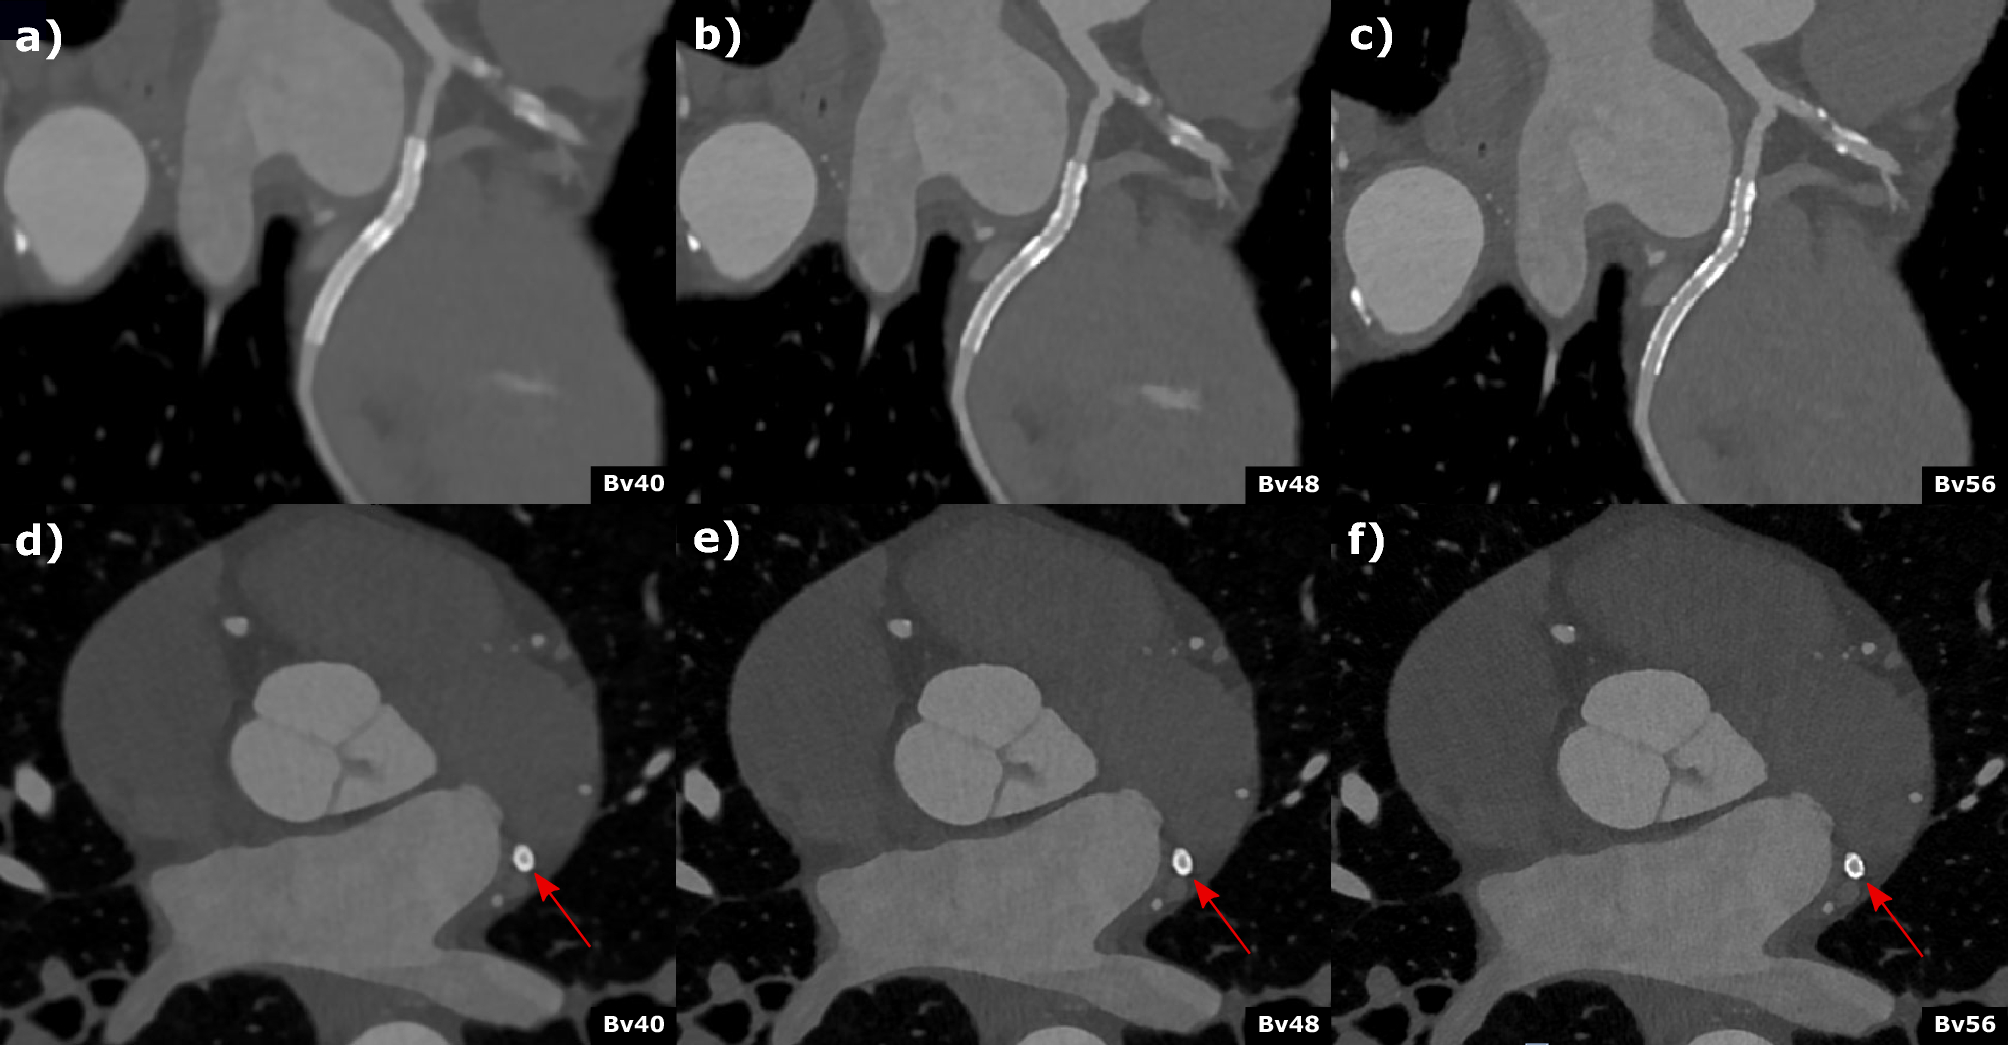

Coronary computed tomography angiography of a 62-year-old male patient with known coronary artery disease and stenting of the circumflex artery. Curved (a–c)) multiplanar reformations and axial (d–f)) reconstructed with different kernel strength (a and d) Bv40, (b and c) Bv48, (c and f) Bv56 depict the stent (2.5 mm diameter) in the circumflex artery. Stent lumen was best visible in the Br56 kernel reconstruction (c and f) and an in-stent restenosis could be reliably excluded. Scan was performed with 144 × 0.4 mm dual source, multi spectral high-pitch-flash-mode (3.2). Effective radiation dose was 1.07 mSv.